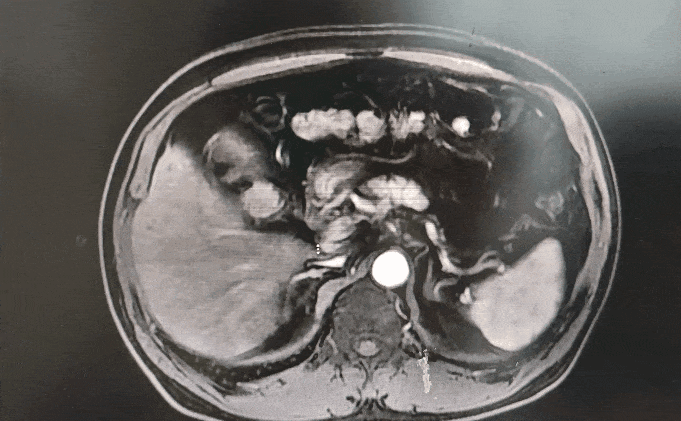

◈ 2022-11-28,TTFields联合化疗治疗2个月,上腹部MR增强扫描,对比基线( 2022-09-13):胰周多发囊性病变,考虑为术后改变(活检后),假性囊肿形成可能,较前略吸收;局部与邻近胃壁分界不清,左侧门脉高压,胃底、肠系膜静脉曲张,脾静脉近段较前显示清楚,肠系膜上动脉、腹腔干近段及局部分支周围软组织影较前范围缩小。

2022-11-28上腹部MR增强扫描—TTFields联合化疗治疗两个月